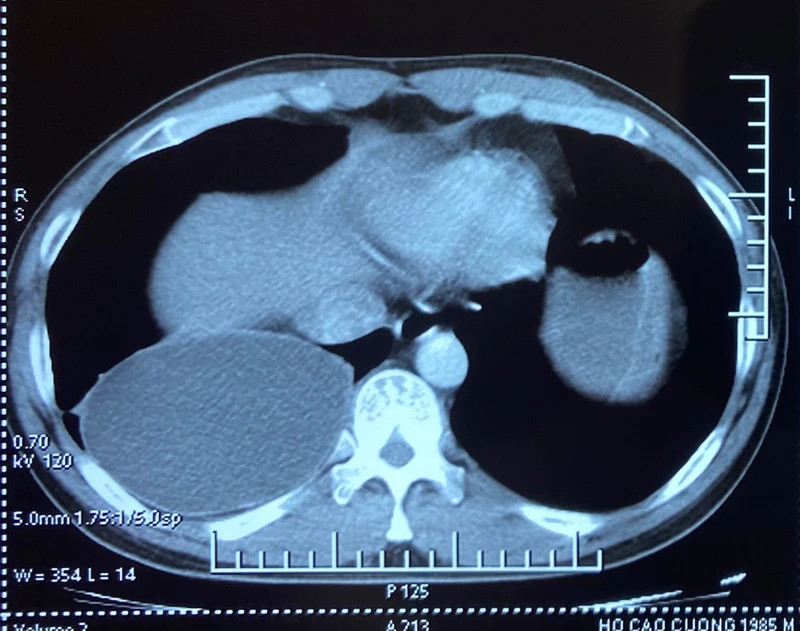

Khi trứng xâm nhập cơ thể người, chúng di chuyển đến ruột, sau đó thoát vỏ thành ấu trùng xuyên qua thành ruột và theo đường máu đến các cơ quan, trong đó nguy hiểm nhất là gây tổn thương ở phổi, mắt, gan, não.